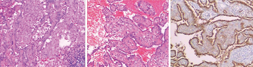

女性,51岁。因"咳嗽、咳痰"1周,于2015年11月28日收入广东医科大学附属深圳南山医院呼吸科。患者咳嗽以刺激性干咳为主,少量黏白痰。无咳血,无发热、盗汗,无体重减轻。门诊治疗无好转,行胸部X线片提示右肺门区占位性病变,遂行胸部CT平扫及增强表现:右肺中叶、下叶支气管间可见一类圆形肿块,直径约4.2 cm,密度较均匀,CT值约为36 Hu,动脉期CT值约80 Hu,实质期约90 Hu,考虑偏良性病变(硬化性血管瘤、孤立性纤维瘤),不完全排除类癌(图1)。既往有子宫肌瘤和胆囊结石病史。体格检查:神清,无贫血貌,全身皮肤、巩膜无黄染,浅表淋巴结未触及肿大,口唇无发绀,颈软,胸廓无畸形,双肺语颤增强及减弱,双肺叩诊清音,双肺呼吸音清,未闻及干湿性啰音。心前区无隆起,无震颤,心界无扩大,心率93次/min,律齐,未闻及杂音。腹平软,全腹无压痛,无反跳痛,肝脾肋下未触及,莫菲氏征阴性,肝肾区叩痛阴性。双下肢无水肿。入院后积极完善各项检查:血、尿、粪常规正常。红细胞沉降率为56 mm/h,C反应蛋白(C reactive protein,CRP)12.7 mg/L,糖类抗原CA153为41.76 IU/ml ,痰找抗酸杆菌、结核感染T细胞、γ-干扰素(interferon-γ,IFN-γ)三项检测均阴性。支气管镜检查提示右中叶、右下叶基底段外压性狭窄。考虑位于肺门,位置深,穿刺活检困难,遂经本科会诊后转入手术治疗,12月3日全麻双腔气管插管胸腔镜下行右肺门肿物切除,术中见水平裂与斜裂交界处约5 cm×4 cm大小圆形肿块,予以吸引器、超声刀钝锐性分离,肿瘤内侧与肺动、静脉关系密切,血供丰富,有滋养血管,紧贴右中、下叶支气管分叉处完整切除,术中冰冻病理考虑良性肿瘤,未做纵隔淋巴结清扫,术后常规病理见肿瘤为实性、乳头状、硬化性和出血性组织结构混合,增生的Ⅱ型肺泡细胞被覆在乳头状结构表面,并可见慢性炎症和泡沫细胞等变化(图2)。免疫组织化学检查明确为硬化性血管瘤(图3),术后恢复顺利,第8天痊愈出院。随访11个月,患者无不适,复查胸部CT未见异常。

肺硬化性血管瘤(pulmonary sclerosing hemangioma,PSH)系肺部少见的良性肿瘤,由Leibow和Hubbell[2]于1956年首先报道,其病理组织形态类似于皮肤组织中的硬化性血管瘤而得名,主要表现有实性细胞、血管瘤样改变或出血、乳头状突起、硬化,按不同的比例混合存在[3]。其组织起源和性质尚未达成共识,有研究[4]通过免疫组织化学等技术表明实际上是来源于肺泡上皮( Ⅱ型肺泡细胞)或细支气管上皮细胞的良性肿瘤,因局部的慢性炎症表现也有学者认为是非特异炎症所致的肺内瘤样增生病变,又称为硬化性血管瘤型肺炎性假瘤。也有数例报道[5,6]骨转移、淋巴结转移的,但预后良好,故可认为是低度恶性肿瘤。发病中年女性多见,临床表现多数患者无症状,少数表现为咳嗽、咳痰或胸痛,亦有发热表现[7]。本例患者出现刺激性干咳与瘤体较大压迫、刺激局部的支气管有关。影像学常为主要的诊断方式,胸部CT多表现为单发类圆形肿物,边缘光滑,少有毛刺、分叶,增强CT延迟强化,一般无肿大的肺门及纵隔淋巴。因肿块多位于肺周边部,经皮肺穿刺活检亦为可行,但本例位于肺门深处,靠近血管,术中发现肿瘤血供丰富,术前未做穿刺活检避免了大出血的风险。或者CT表现有明显强化,有血管瘤成分的病变亦不适合穿刺。临床注意与结核球、错构瘤、炎性假瘤、周围型肺癌鉴别。治疗以手术完整切除瘤体为主,尽量保留肺功能,本例患者完整剔除肿瘤,避免了肺叶切除。尽管肿瘤界限清楚,但与周围肺间质和支气管关系密切甚至有浸润现象,尤其是瘤体较大且位于肺门处,术中需注意暴露,防止出血及损伤支气管壁,有滋养血管的需仔细分离,可靠结扎或者超声刀凝断,本例采用胸腔镜手术,术野有放大作用,解剖结构和层次更为清晰,有一定的优势,比小切口更为微创[8]。虽预后良好,但术后需随访有无复发。